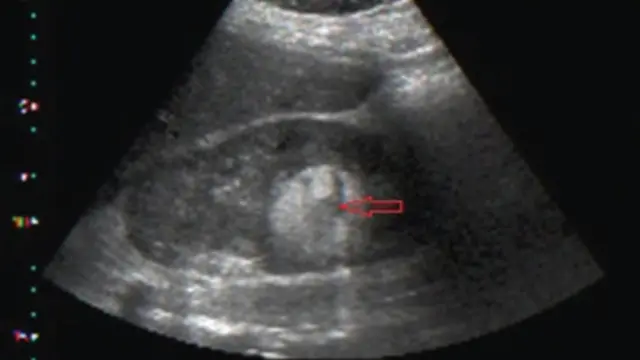

Things wey fit cause Fibroid inside woman belle

Nobodi know exactly wetin dey cause di disease wey dey affect women within di reproductive age but sabi pipo say e get certain factors wey fit put woman at risk.

Symptoms

Di symptoms depend on di size, number and location of di fibroid for di womb. But many women wey get fibroid no dey get any symptoms dat na wetin Dr Brown add put.